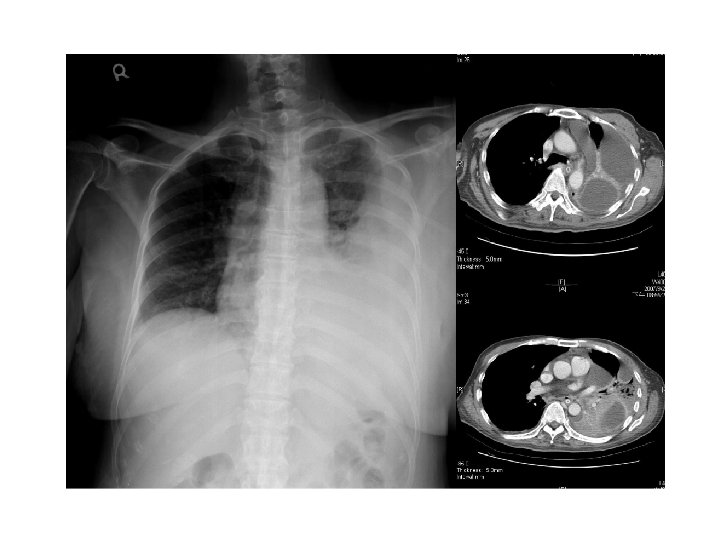

Contrast-enhanced CT scanning may be of value in patients when the diagnosis is in doubt or an underlying abnormality is thought either to be associated with the empyema or potentially its cause, such as an esophageal perforation or bronchogenic carcinoma. CT scanning can help to differentiate pleural empyema from a parenchymal lung abscess and may also help to formulate management decisions about drainage. Empyemas are usually lenticular in shape and compress the lung parenchyma, while lung abscesses often have an indistinct boundary between the lung parenchyma and collection. The “split pleura” sign caused by enhancement of both parietal and visceral pleural surfaces and their separation in empyema is characteristic of a pleural collection. Pleural thickening is seen in 100% of empyemas and 56% of exudative parapneumonic effusions. Moderate (<2 cm) mediastinal lymphadenopathy is seen in over one-third of patients with pleural infection. Management of pleural infection in adults: British Thoracic Society pleural disease guideline 2010 Thorax 2010; 65(Suppl 2): ii 41 eii 53.